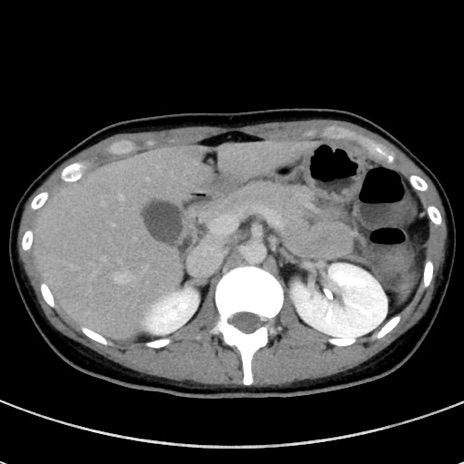

冠状断像

【症例】20歳代女性

【主訴】嘔吐、下腹部痛

【現病歴】昨日夕食後に嘔吐し下腹部痛が出現。本日になっても嘔吐持続し改善しないため来院。

【身体所見】意識清明、BT 37.2℃、BP 108/67mmHg、腹部:平坦、やや硬、下腹部正中から右にかけて圧痛あり、反跳痛軽度あり、tapping pain(+)。

【データ】WBC 13600、CRP 14.94